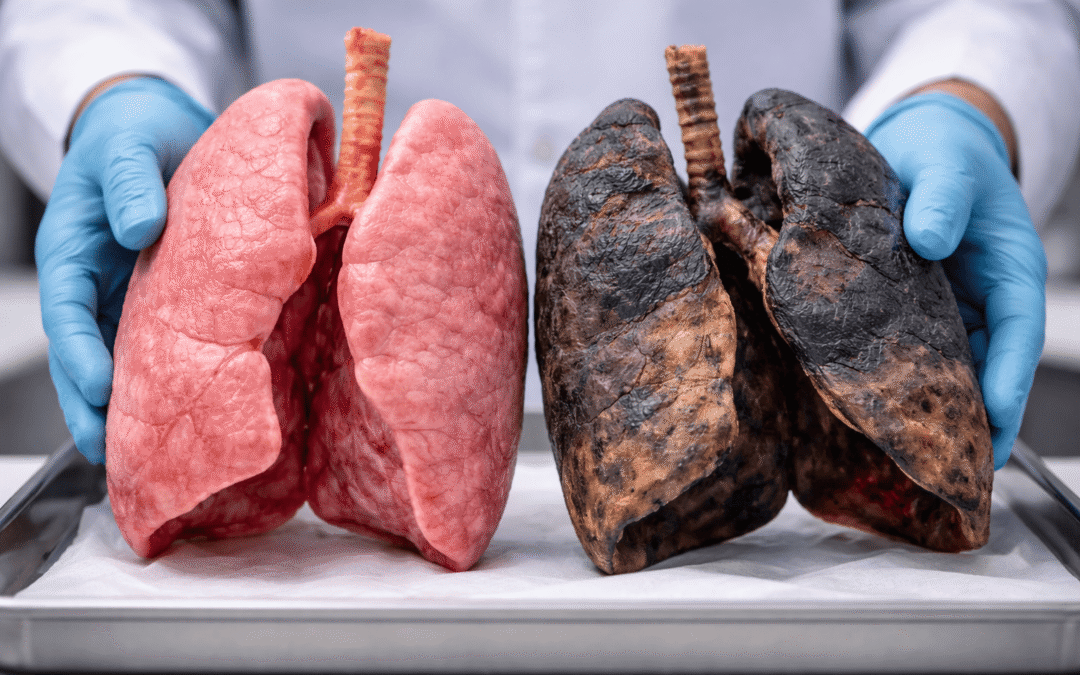

Коли остання сигарета згасає, легені не просто чекають – вони оживають, ніби ріка, що прорвала греблю сміття. Так, вони відновлюються, і цей процес починається вже за лічені години. Цилії, ті крихітні волоски в бронхах, які очищають повітря, оживають за тижні, а функція дихання покращується на 10–30% за перші місяці. Але повне оновлення залежить від стажу куріння, віку та зусиль – у когось легені набувають сили марафонця за роки, у інших лишаються шрами від емфіземи.

Як куріння нищить легені: від смоли до мутацій

Кожна затяжка – це атака: понад 7000 хімікатів, з них 70 канцерогенних, осідають у бронхах і альвеолах. Смола обволікає цилії, паралізуючи їх, як лід на річці взимку. Легені кашляють, хриплять, накопичуючи мокротиння з токсинами. За роки це веде до запалення, фіброзу та емфіземи – стінок альвеол руйнуються, ніби перегородки в губці.

На клітинному рівні тютюновий дим викликає мутації ДНК у епітелії бронхів. Більшість клітин у затятих курців пошкоджені, але деякі базальні клітини (KRT5+) виживають, створюючи резерв для майбутнього. Дослідження Інституту Сенгера підтверджують: навіть після 40 років по пачці щодня ці “бункери” лишаються цілими. Без них регенерація була б неможливою.